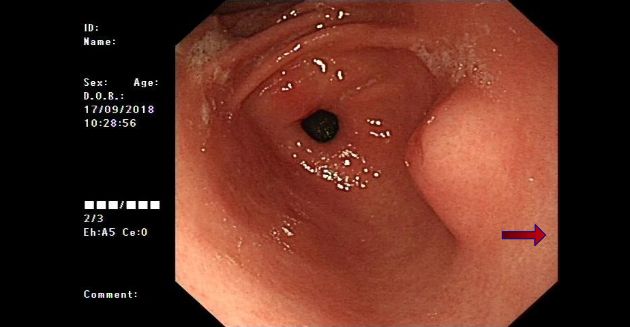

In 2018, she was diagnosed with chronic gastritis and a submucosal bulging mass on the lesser curvature of the gastric antrum by gastroscopy (Figure 1).